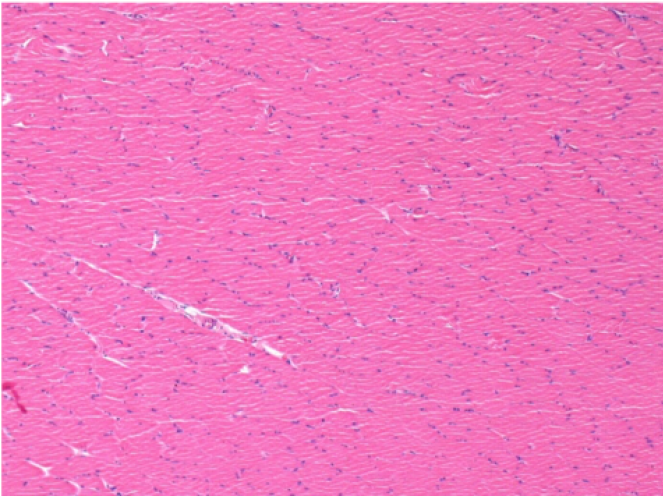

3 months (D90)after Endopeel Injection 0.1ml in the right pretibial muscle.

7 months (D210)after Endopeel IM Injection 0.1ml in the right pretibial muscle.

Complete Restitutio ad integrum after 7 months